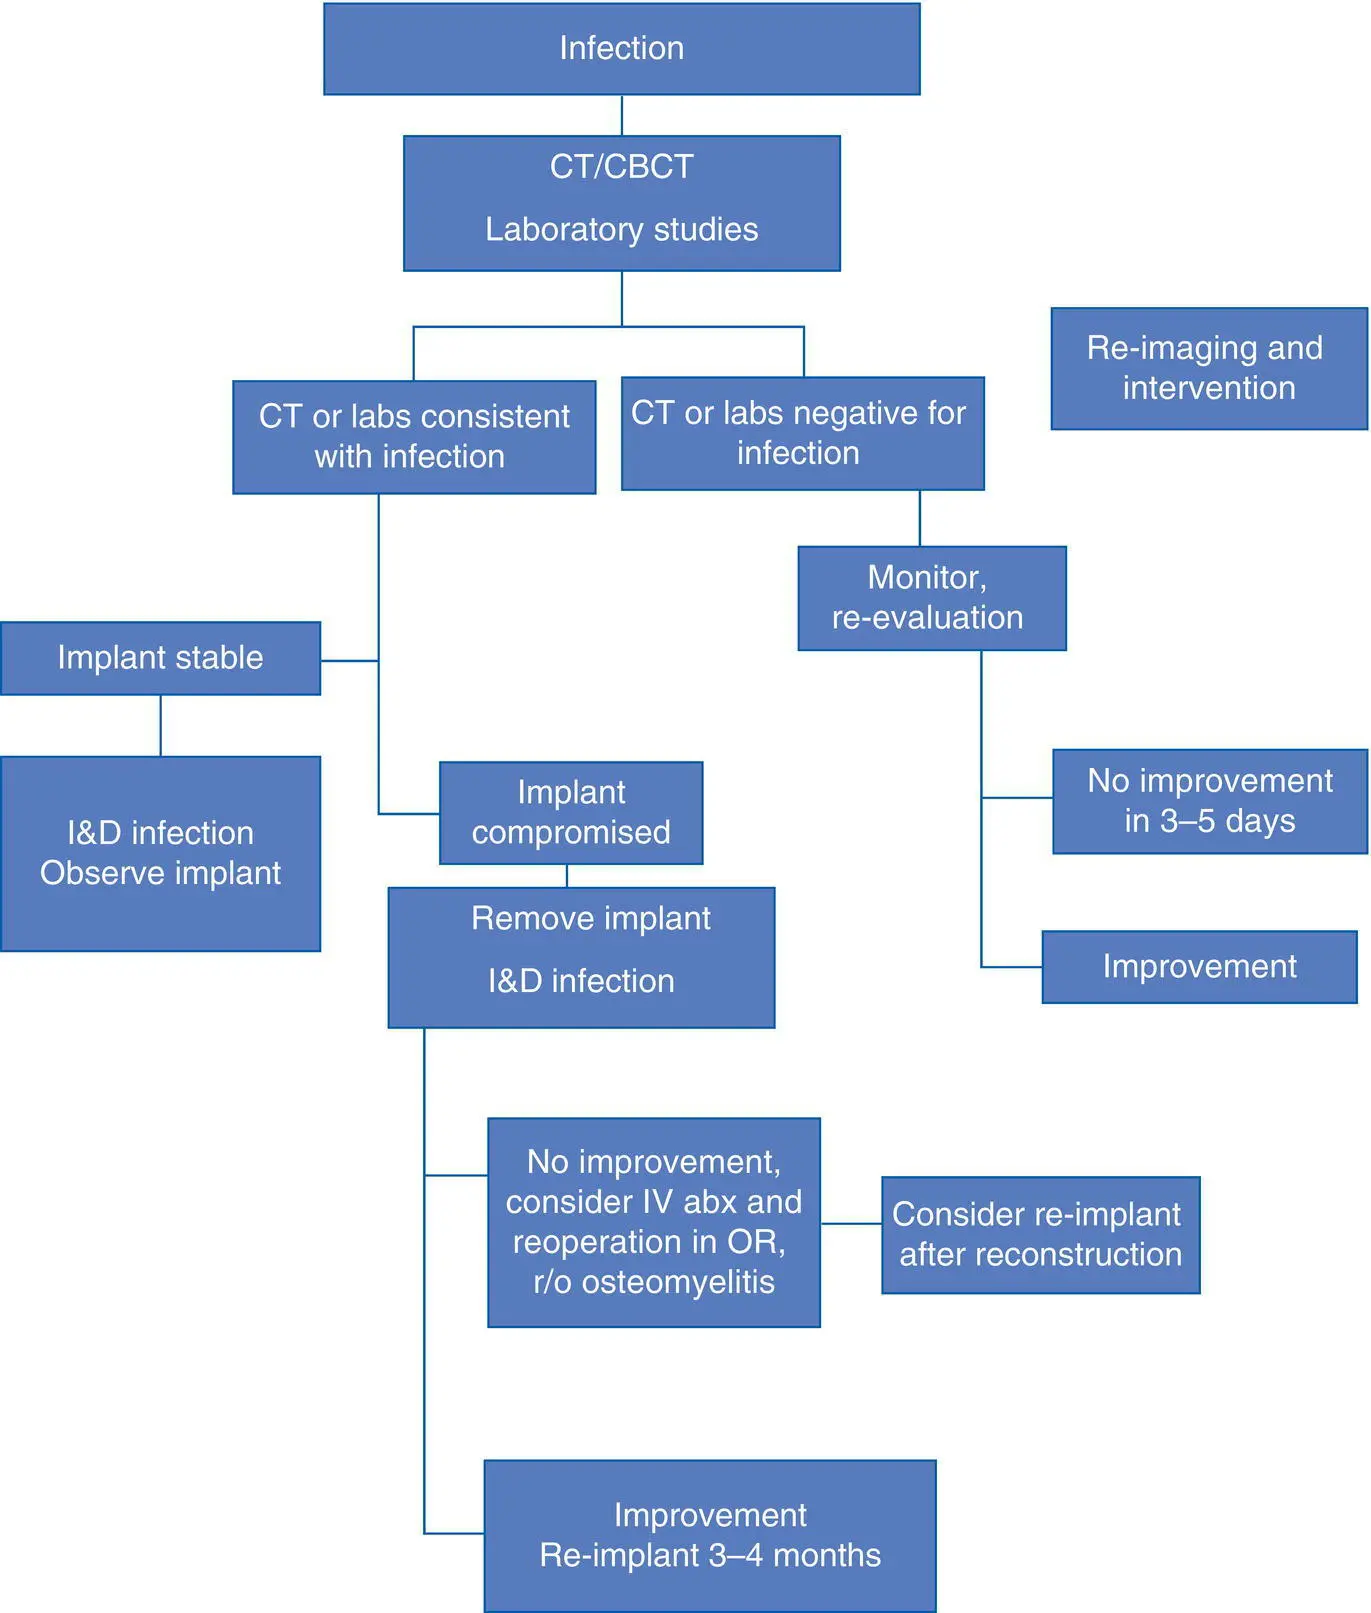

Fig. 3.16. Peri‐implantitis leading to bone loss (crater‐like defect).